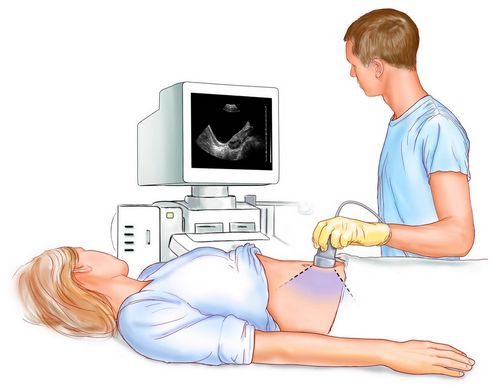

Діагностування позаматкової вагітності є скрутним процесом, так як симптоми позаматкової вагітності подібні проявам нормальної вагітності. Якщо лікар-гінеколог підозрює у пацієнтки позаматкову вагітність, то першим ділом він відправить її на УЗД і призначить аналіз крові хоріонічного генадропіна людини (ХГЧ). Даний аналіз крові показує рівень гормону вагітності. Якщо рівень гормону не відповідає терміну вагітності то, швидше за все, у жінки ектопічна вагітність.

При проведенні ультразвукового дослідження лікар - узіст уважно розглядає матку, фаллопієві труби. Якщо лікар побачить ембріон, який розташовується в матковій трубі, жінці ставлять діагноз ектопічної вагітності. Але найчастіше ембріон або вмирає або має занадто маленькі розміри, які не дозволяють виявити його за допомогою апарату УЗД. Натомість, лікар виявляє ненормальні розміри маткової труби, в якій залишаються згустки крові або тканини, що залишилися від ембріона.

Процедура УЗД фіксує наявність вагітності в матці. Якщо зроблений жінкою тест на вагітність показує дві смужки, то вагітність може бути як позаматкової, так і нормальної, тільки на дуже ранньому етапі формування. Також тест для визначення вагітності може показувати помилковий позитивний результат, особливо якщо друга смужка проявилася неяскраво.

Якщо жінка не помічає ніяких больових відчуттів, лікар-гінеколог продовжує спостерігати за пацієнткою, призначаючи їй аналізи на гормони і УЗД, поки діагноз остаточно не підтвердиться.